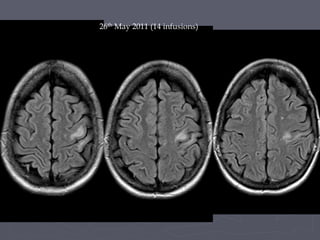

► MRI on 26th May – progression of lesion

?PML

26th May 2011 (14 infusions)